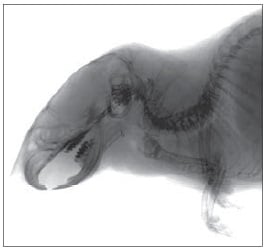

松定プレシジョンのマイクロフォーカスX線検査装置は、分野を問わず様々な非破壊検査にお使いいただけます。ここではその一部をご紹介いたします。ご希望の用途の画像をクリックしてください。

医学研究・医薬・生物関連